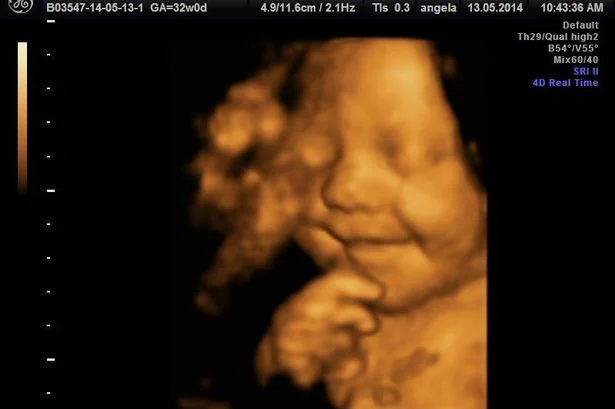

TRIMESTER 3 TRIMESTER 3

capaciteit tot emotionele expressie al aanwezig in de prenatale fase

-gelaatsbewegingen die lijken op fronse, glimlache, wenen, lachen

- bereid kind voor op emotionele expressiviteit